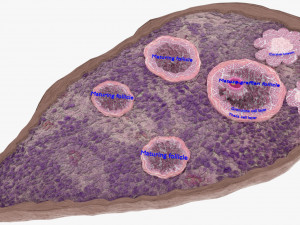

The model meshes include adult circulation versus circulation in Tetralogy of Fallot (TAF), arrow labels and text labels. The blood flow in a patient with Tetralogy of Fallot is outlined in this model. To contrast it to normal blood circulation a separate model of normal circulation is included. The Tetralogy of Fallot (OVER RIDING OF AORTA, PUL STENOSIS, VENTRICULAR SEPTAL DEFECT, RIGHT VENTRICULAR HYPERTROPHY), fossa, ligament teres , venosus, and arteriosus are duly depicted with proper labelling and blood flow directional arrows. Excellent model for teaching, demonstration and knowlegde of human body. The models include both procedural and image textures blend files separately. The texture file include diffuse, roughness and normal png and jpeg based on non overlapping UV maps.